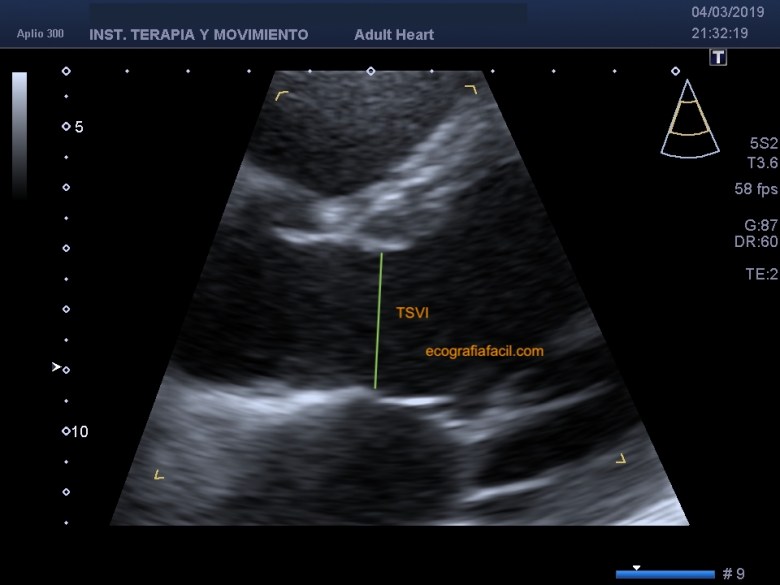

Este punto temporal coincide con una imagen donde vemos completamente abiertos los velos de la válvula mitral (VM) y por ello es posible medir también el Tracto de Salida del VI (TSVI), que podemos llegar a necesitar para cuantificar posteriormente una estenosis de la Válvula Aórtica (EAo). Lo más cómodo es hacer un zoom sobre esta región para mayor comodidad y fiabilidad en la medición (fig 13).

This temporal point coincides with an image where the veils of the mitral valve (VM) are completely open and it is therefore possible to measure the LV Exit Tract (LVOT), which we may need to subsequently quantify a stenosis of the Valve Aortic (EAo). It is most convenient to zoom in on this region for greater convenience and reliability in the measurement (fig 13).